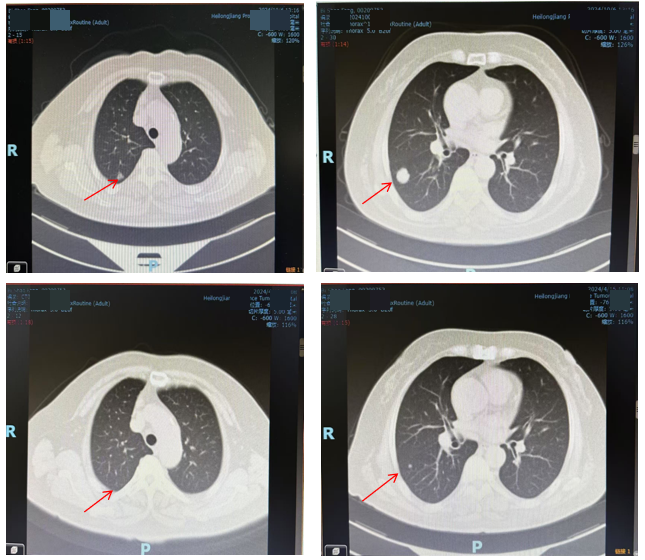

2024年10月6日胸部CT提示右肺病灶较前增大(图3),提示疾病进展。

目前诊断:结肠癌伴肝转移、肺转移(cT3N1M1b-IVb期)。